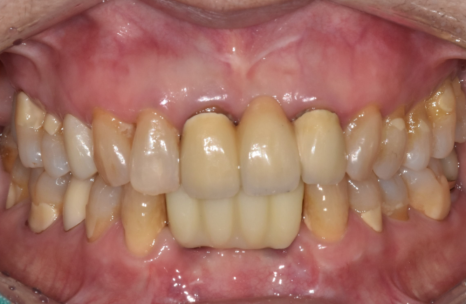

색상도 자연스럽고,

모양도 만족스러운 결과가 나왔습니다.^^

치아가 흔들리고 솟아 보인다고 해서

무조건 뽑아야 하는 건 아닙니다.

상태에 따라 살릴 수 있는 방법부터 고민하고,

그게 어렵다면 임플란트로

안정적으로 해결할 수 있습니다.